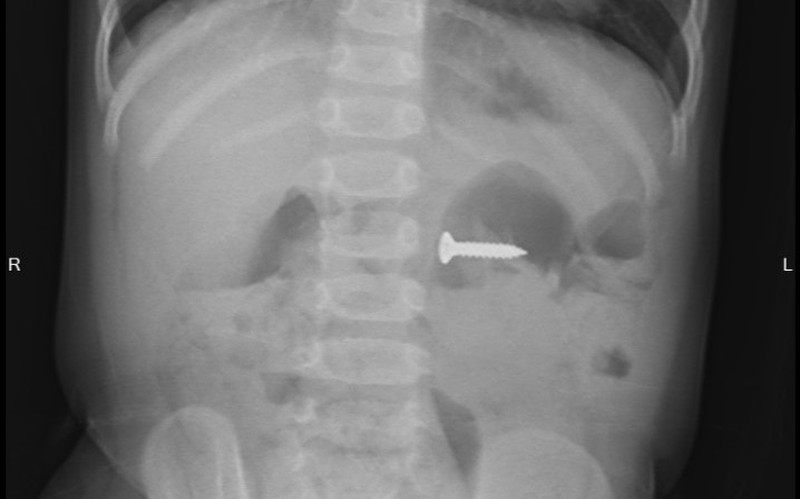

Tại Bệnh viện Sản Nhi tỉnh Phú Thọ, các bác sĩ chỉ định cho bé chụp X-quang thăm dò và phát hiện dị vật đinh vít kích thước 2cm trong dạ dày, vị trí ngang đốt sống D3. Sau khi hội chẩn với các bác sĩ Khoa Ngoại nhi tổng hợp và giải thích với gia đình, bé được chỉ định gây mê nội soi tiêu hóa cấp cứu gắp dị vật.

Sau 5 phút, BSCKI.Triệu Ngọc Bích, Khoa Chẩn đoán hình ảnh – thăm dò chức năng gắp ra được dị vật là 1 chiếc đinh ốc vít có một đầu sắc nhọn nằm trong dạ dày của bé. Các bác sĩ đánh giá, với tính chất sắc nhọn của đầu đinh, nếu không loại bỏ kịp thời có thể gây tổn thương đâm thủng thành ruột, dạ dày, thậm chí có thể gây tổn thương nhiều vị trí mà chiếc đinh đi qua.